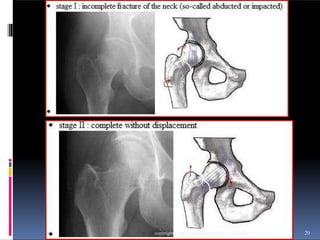

 -GARDEN

This is based on the degree of valgus

displacement

 Type I: Incomplete/valgus impacted

 Type II: Complete and nondisplaced

on AP and lateral views

 Type III: Complete with partial displacement;

trabecular pattern of the femoral head does

not line up with that of the acetabulum

 Type IV: Completely displaced; trabecular

pattern of the head assumes a parallel

orientation with that of the acetabulum 19